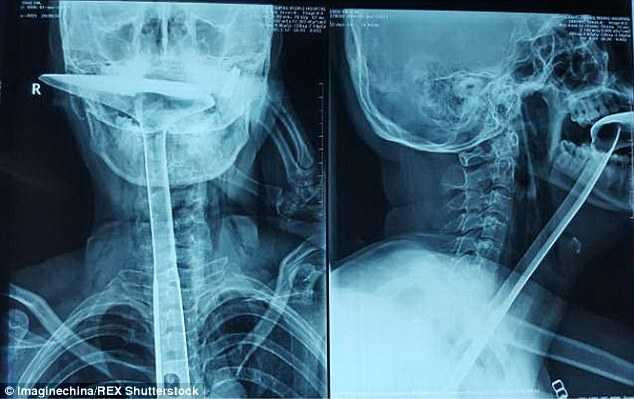

Bác sĩ Nguyễn Thế Huy, Phó Trưởng khoa Tai Mũi Họng, Bệnh viện Nhi đồng 1 cho biết: Chụp CT ngay lập tức lúc đó cho thấy cổ họng bị tổn thương nặng, tràn khí trung thất, tràn khí dưới da vùng cổ, tràn dịch màng phổi, áp xe trung thất. Có một đường rách ở thực quản dài 7cm. Các bác sĩ tiên lượng tình trạng bệnh nhi xấu, nếu chậm trễ sẽ tử vong.